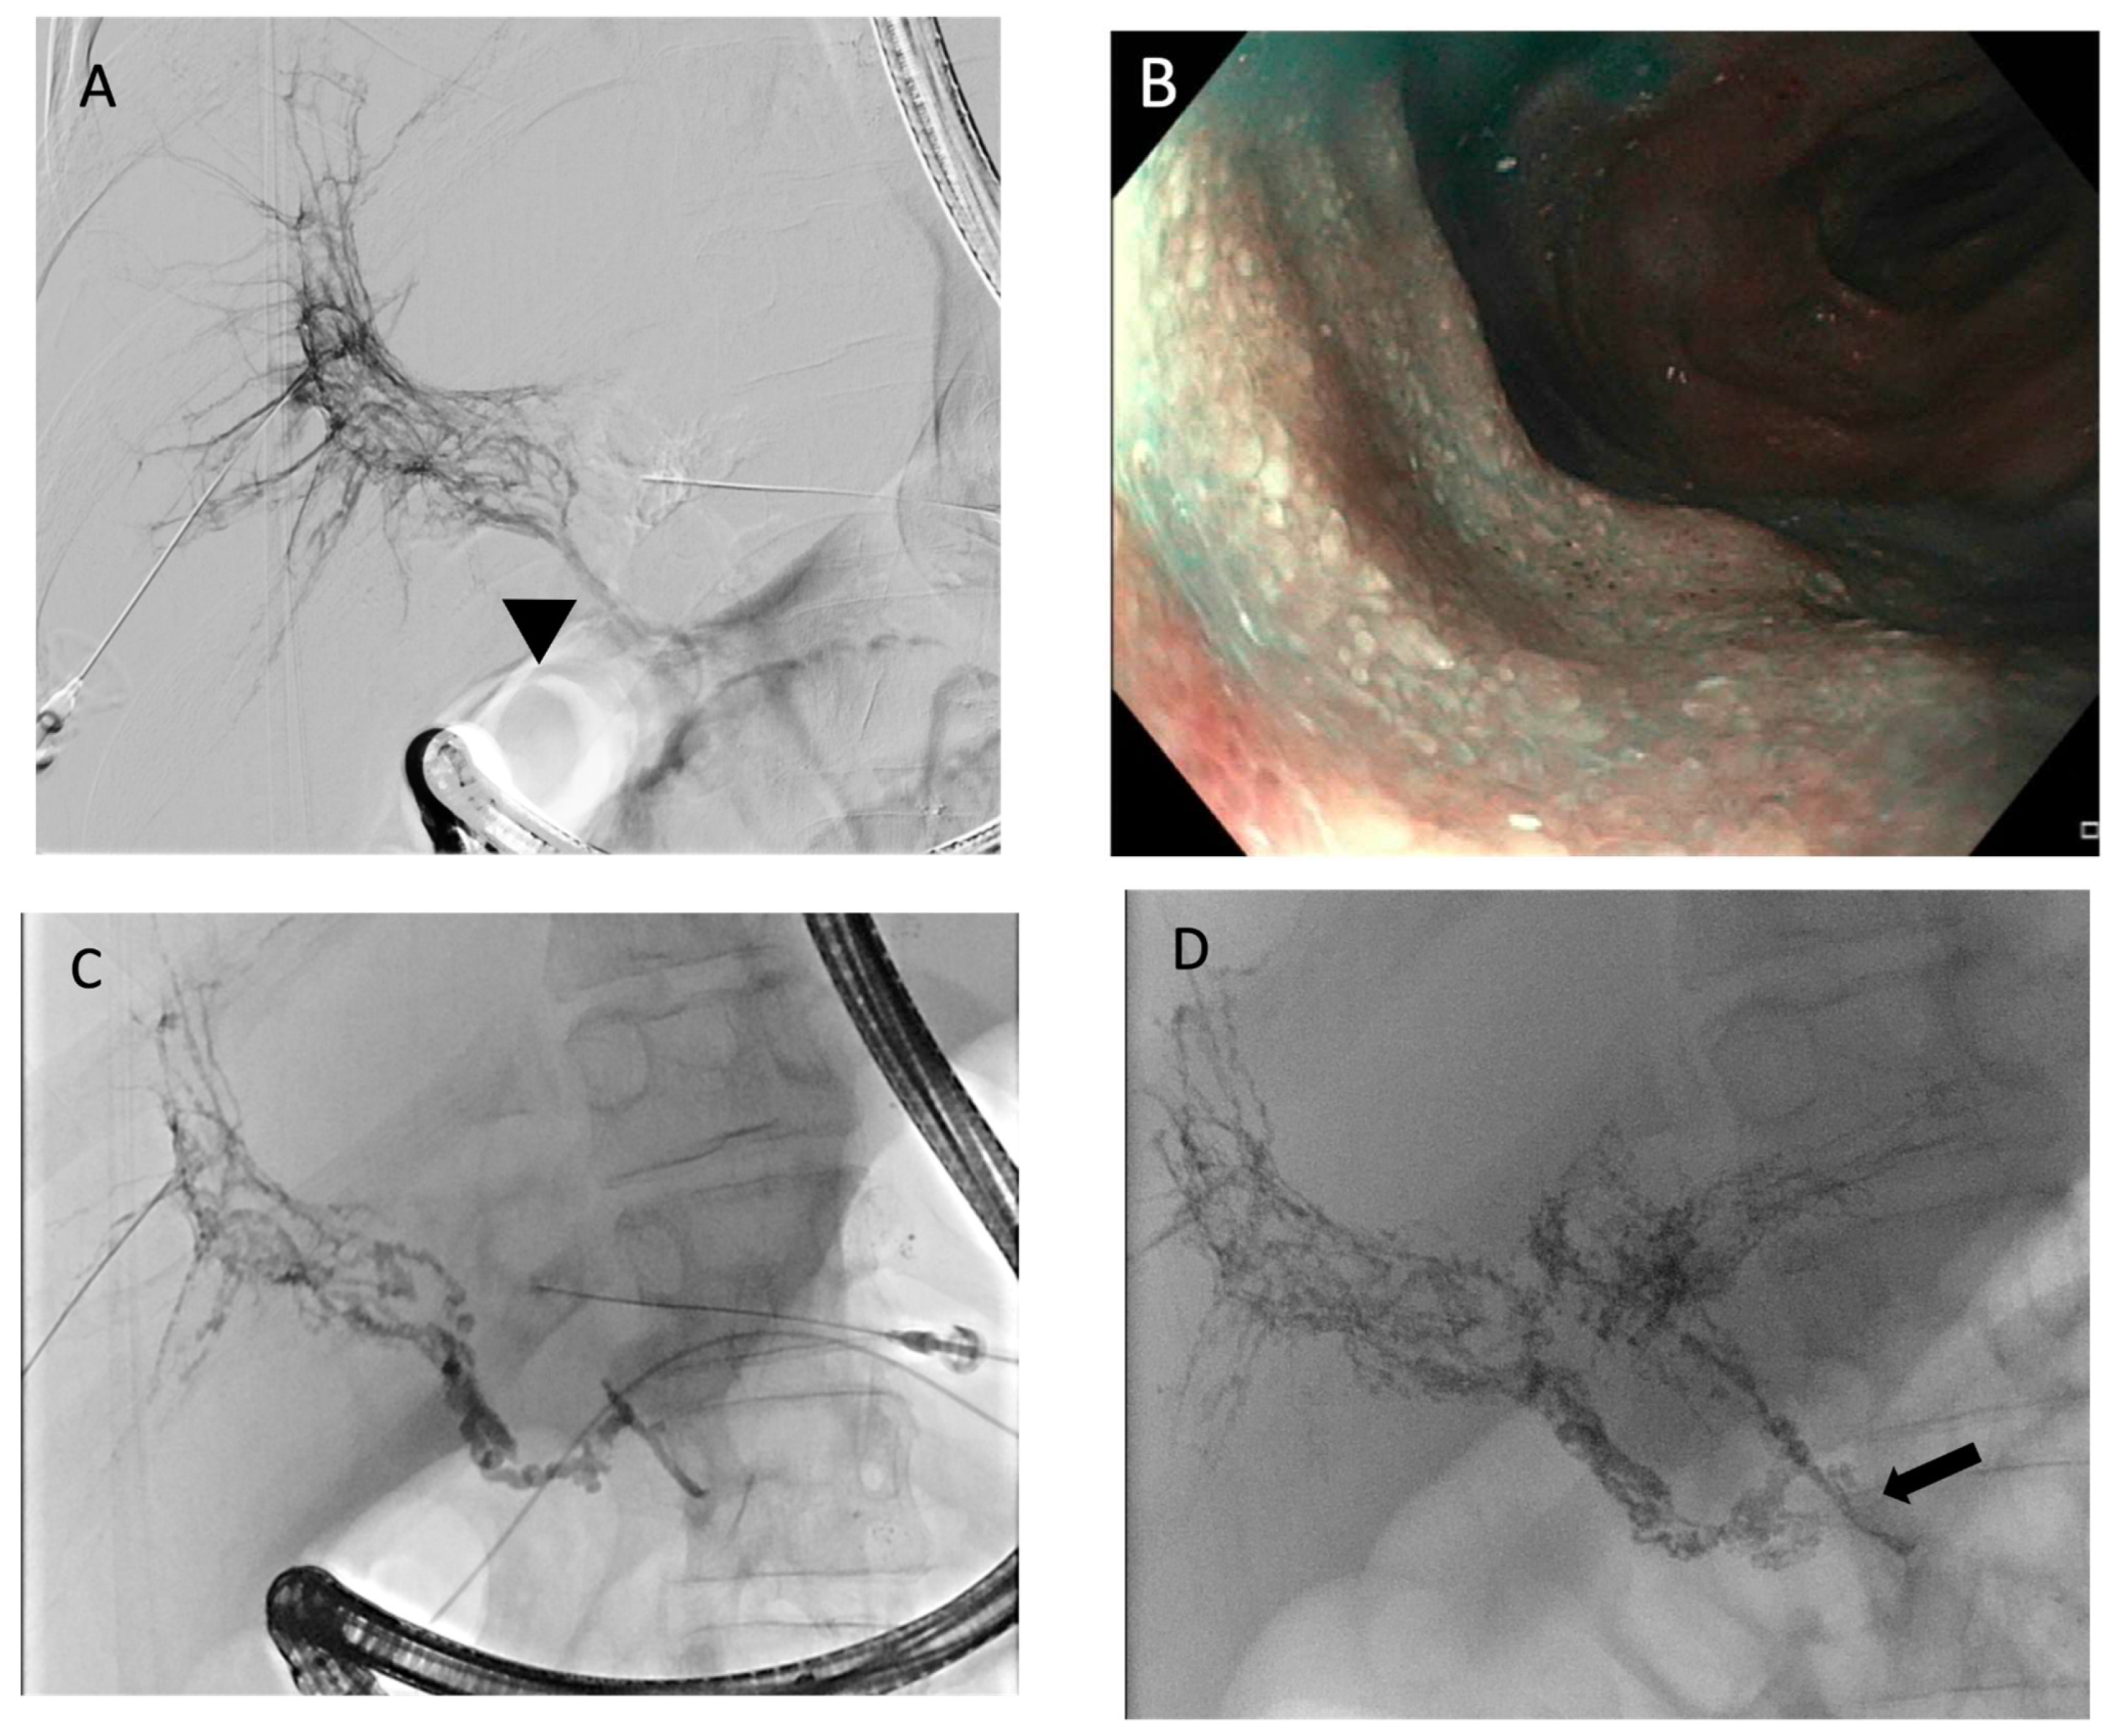

Figure 11. A 21-year-old girl with a history of hypoplastic left heart syndrome and Fontan’s operation. (A) Conventional fluorosocpic intrahepatic lymphangiogram demonstrated abnormal hepatico-duodenal connections and dilated lymphatic channels (black arrow) along the duodenal wall. (B) Minimum-intensity-projection (MIP) coronal image of post-contrast T1-weighed intrahepatic DCMRL showed contrast leakage into duodenal lumen (white arrowheads). (C) Coronal image of post-contrast T1-weighed intrahepatic DCMRL showed abnormal enhancement of mesenteric lymphatics (white arrow), indicating retrograde mesenteric flow. (D) Endoscopic photo at second part of duodenum showed multiple tiny mucosal white specks (black arrow), compatible with snowflake appearance of lymphangectasia.

The most common abnormal imaging finding in patients with PLE is duodenal wall enhancement with leakage of contrast into the duodenal lumen [29,76] (Figure 11). This reflects the pathophysiology of abnormal flow patterns through the hepaticoduodenal lymphatic connection as a result of increased central venous pressure, absent thoracic duct, or abnormal lymphogenesis. This also corresponds to the endoscopic findings of “snowflake” appearance, representing dilated mucosal and submucosal lymphatic vessels, which are prone to rupture and leakage [77].

Other abnormal imaging features include chylous ascites, mesenteric lymphatic edema, retrograde mesenteric lymphatic flow, and retrograde flow into the peripancreatic lymphatic network. It is not uncommon to observe other associated abnormalities in the central conducting lymphatic system, including absence or dysplasia of the thoracic duct, abnormal lymphatic collateralization away from the midline, and chylous effusions [29,76].